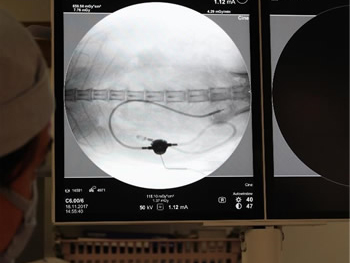

造影で漏れがないか何度も確認

必ず透視下にて漏れがないか何度も確認をします。 透視をしないとシステムや装着部分からの漏れが確認されたり、トラブルが考えられます。

実際、他院で装着して漏れがあるなどの相談をうけることがしばしばあります。

透視下にて実施すれば適切な位置に装着できます。

綺麗につければ感染や漏れもほとんどなく、経過はとても良好です。

透視下にて腎盂に入っていることを確認。

ここにカテーテルを装着していきます。